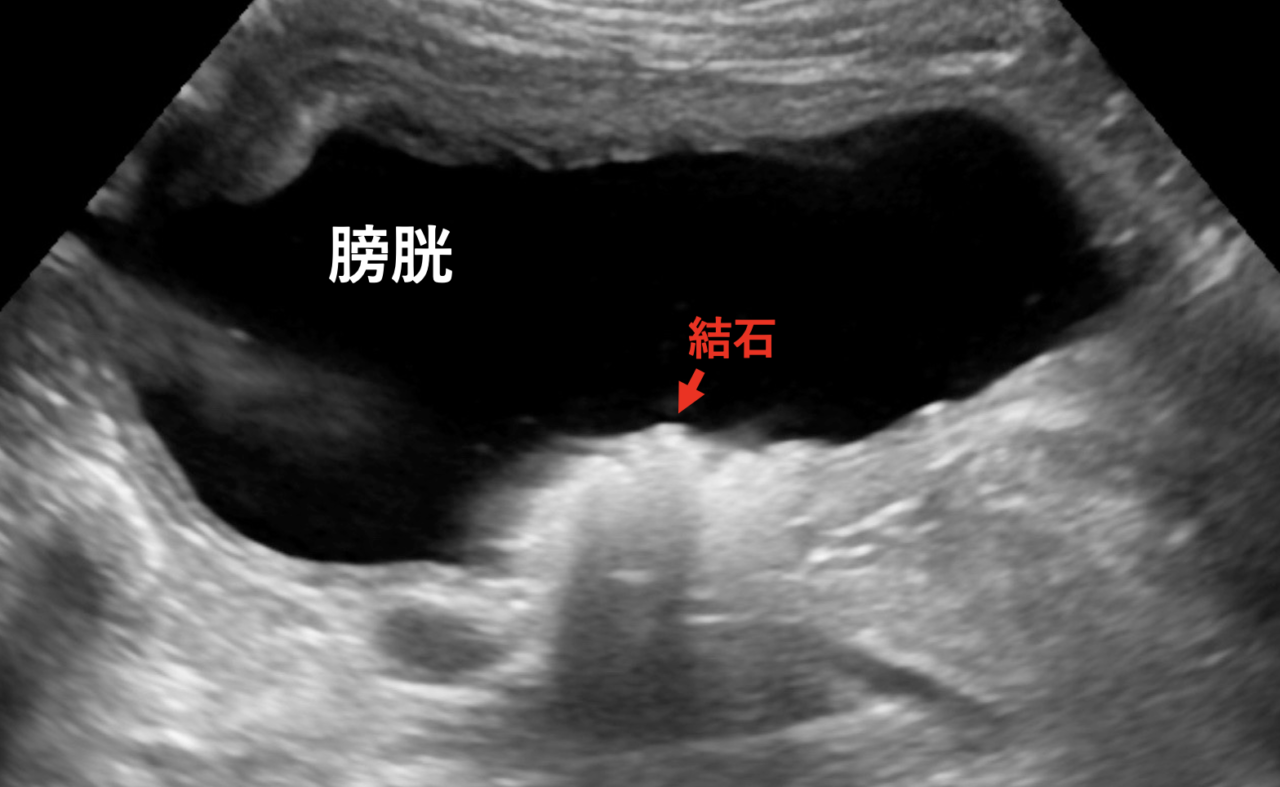

そこでレントゲン検査、腹部超音波検査を実施したところ膀胱内と尿道に結石を疑うような像が認められました。

腹部超音波画像